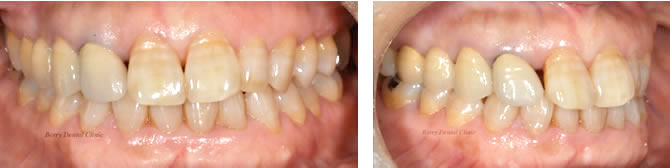

下の画像は保険で使用される銀歯治療と実際のお口の中の症例です。

審美性はもちろん、耐久性(銀歯の内面が変形や腐食しやすい)が悪いため、歯根の露出や人工物の変色、変形が認められて噛み合わせが悪くなっています。そして何よりもやり直しの再治療の際にさらに歯を削らなくてはいけない状態が多いことです。それによって同じ治療方法で治療できないない事があり、別の治療方法(入れ歯や人工物の設計が増えるなど)になる事もあります。